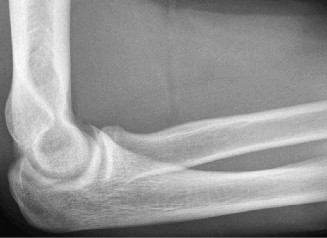

Treat a patient with infected total shoulder arthroplasty? CASE 21 A 70-year-old, right-hand-dominant female presents to clinic complaining of 4 years of gradually worsening chronic right shoulder pain and stiffness. She says the pain is worse at night and with any range of motion, denies a history of trauma, pain in other extremities, or numbness or tingling of the right upper extremity. She notes that her mother suffered from rheumatoid arthritis that affected her shoulder. Physical examination reveals decreased muscle bulk over the right supra- and infraspinatus fossae compared to the contralateral side, limited active and passive ROM, marked weakness with external rotation, and 4+/5 strength with shoulder abduction. X-rays of the right shoulder are shown in Figures 2–58 and 2–59.

Figure 2–58

Figure 2–59

The correct answer is (C). Rotator cuff tear arthropathy consists of a combination of rotator cuff insufficiency, glenohumeral joint degenerative changes, and superior humeral head migration. It is more common in women and also more often found on the dominant side. The patient’s clinical examination with weakened external

rotation and muscle atrophy signaling incompetent supra- and infraspinatus muscles point to rotator cuff insufficiency, and her plain films reveal narrowed glenohumeral joint space as well as superior migration of the humeral head. Choice D is incorrect because, while radiographs would show narrowing of the glenohumeral joint space, they would also likely show numerous osteophytes and posterior wear of the glenoid. Choice B is incorrect because, while adhesive capsulitis does present as decreased active and passive range of motion, the patient’s constellation of symptoms pointing towards rotator cuff insufficiency along with the radiographs make cuff tear arthropathy the more likely choice. Finally, Choice A is incorrect because even though she has a positive family history of rheumatoid arthritis, it is less likely to present only in a single joint. Also, rheumatoid arthritis on radiography appears more as an erosive process without the characteristic superior migration of the humeral head.

The correct answer is (A). Superior migration of the humeral head would be most indicative of chronic rotator cuff insufficiency associated with cuff tear arthropathy, as it is a direct result of the inability of the rotator cuff tendons to help maintain the humerus in its normal position. Acetabularization of the undersurface of the acromion is commonly associated with superior migration of the humeral head found in rotator cuff tear arthropathy, and can be assessed using the Hamada classification, which is based on measurements of the acromiohumeral interval on radiography (Table 2–8). Choices B and C are incorrect because, while narrowed glenohumeral joint space and subchondral sclerosis are associated with rotator cuff arthropathy on radiographs, they indicate degenerative joint changes rather than chronic rotator cuff insufficiency. Choice D is incorrect because it is not a specific sign of rotator cuff arthropathy.